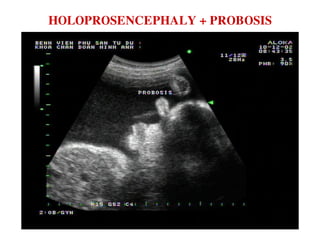

HOLOPROSENCEPHALY + PROBOSIS

PROBOSIS + MOÄT MAÉT